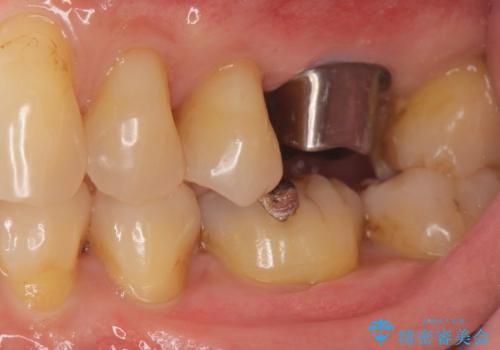

奥歯の欠損 インプラントによる咬合機能回復

- 奥歯を失い噛めないことの治療を希望され来院されました。

臨在する歯が虫歯もなく健全であるため、ブリッジではなくインプラントを用いた機能回復を計画します。

- 50万円(ストローマンインプラント・骨造成・チタンカスタムアバットメント・ジルコニアクラウン)費用は治療当時の料金となります

インプラントを用いることで、隣の歯を削ることなくしっかりと噛む機能を回復させることができます。